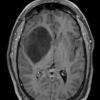

NEOPLASMS (GLIAL)

Astrocytoma, IDH-mutant, WHO Grade 2 (4)